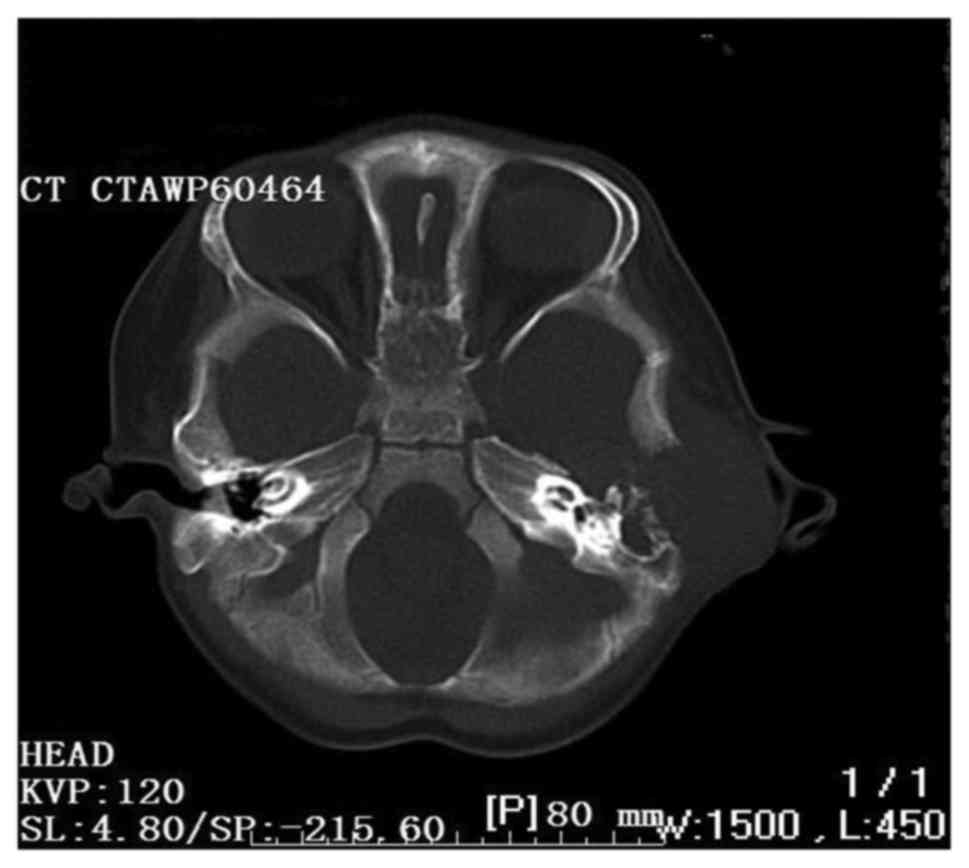

A 20-month-old Chinese boy presented with a 1-month history of worsening left facial paralysis and imbalance and progressive hearing loss, which co-presented with purulence of the left external auditory meatus and a slowly enlarging post auricular mass, swelling of the ear and the temporal bone. Free-field pure-tone audiometry showed moderate conductive deafness and there was no pathological nystagmus. The blood routine examination revealed leukocytosis (27.2/ml). The computed tomography scan revealed a destructive bone lesion involving the left posterior external canal, middle and posterior cranial fossa, and the lateral semicircular canal (Fig. 1).

Figure 1.

An axial computed tomographic scan revealing a destructive bone lesion involving the left posterior external canal, middle and posterior crani fossa, lateral semicircular canal and the facial nerve.